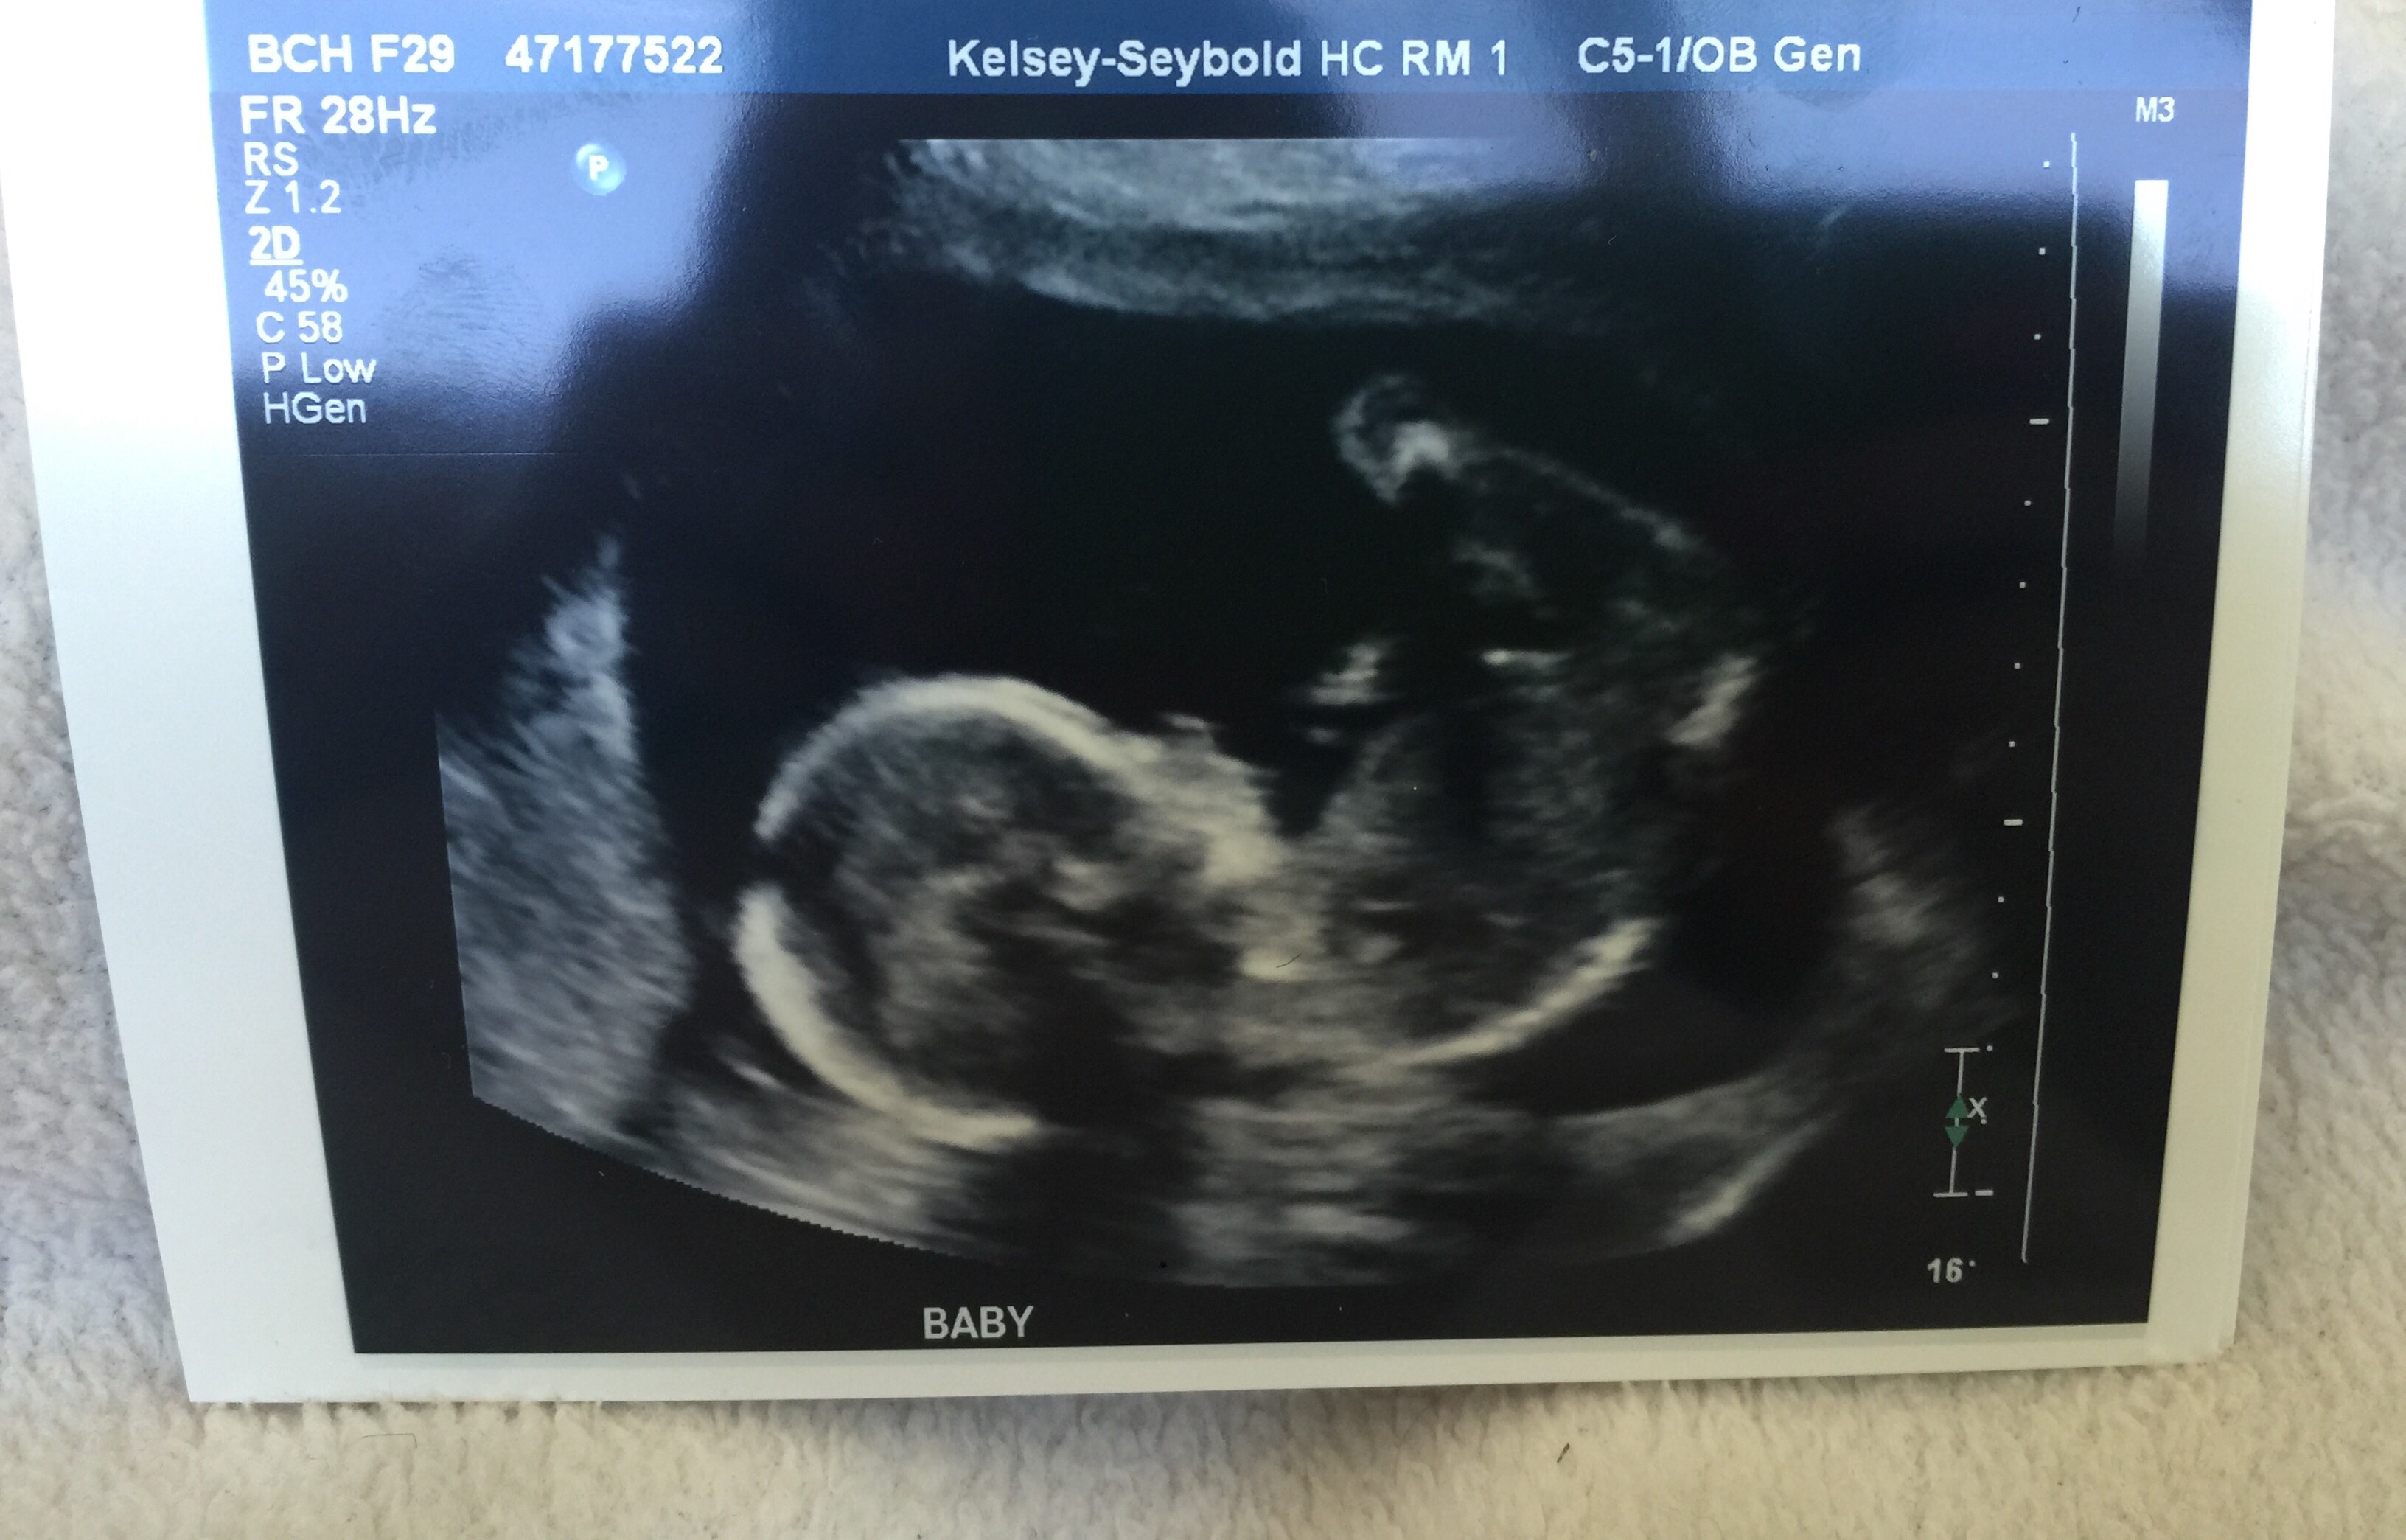

Had my anatomy this morning and was extremely relieved to see him look so handsome and healthy thank God. I was also very nervous last night especially since I didn't start feeling him kick until a couple days ago. It turns out my placenta implanted on top therefore baby has to kick through it for me to feel it. I am now going relax and enjoying the last half of my pregnancy. I couldn't be happier.